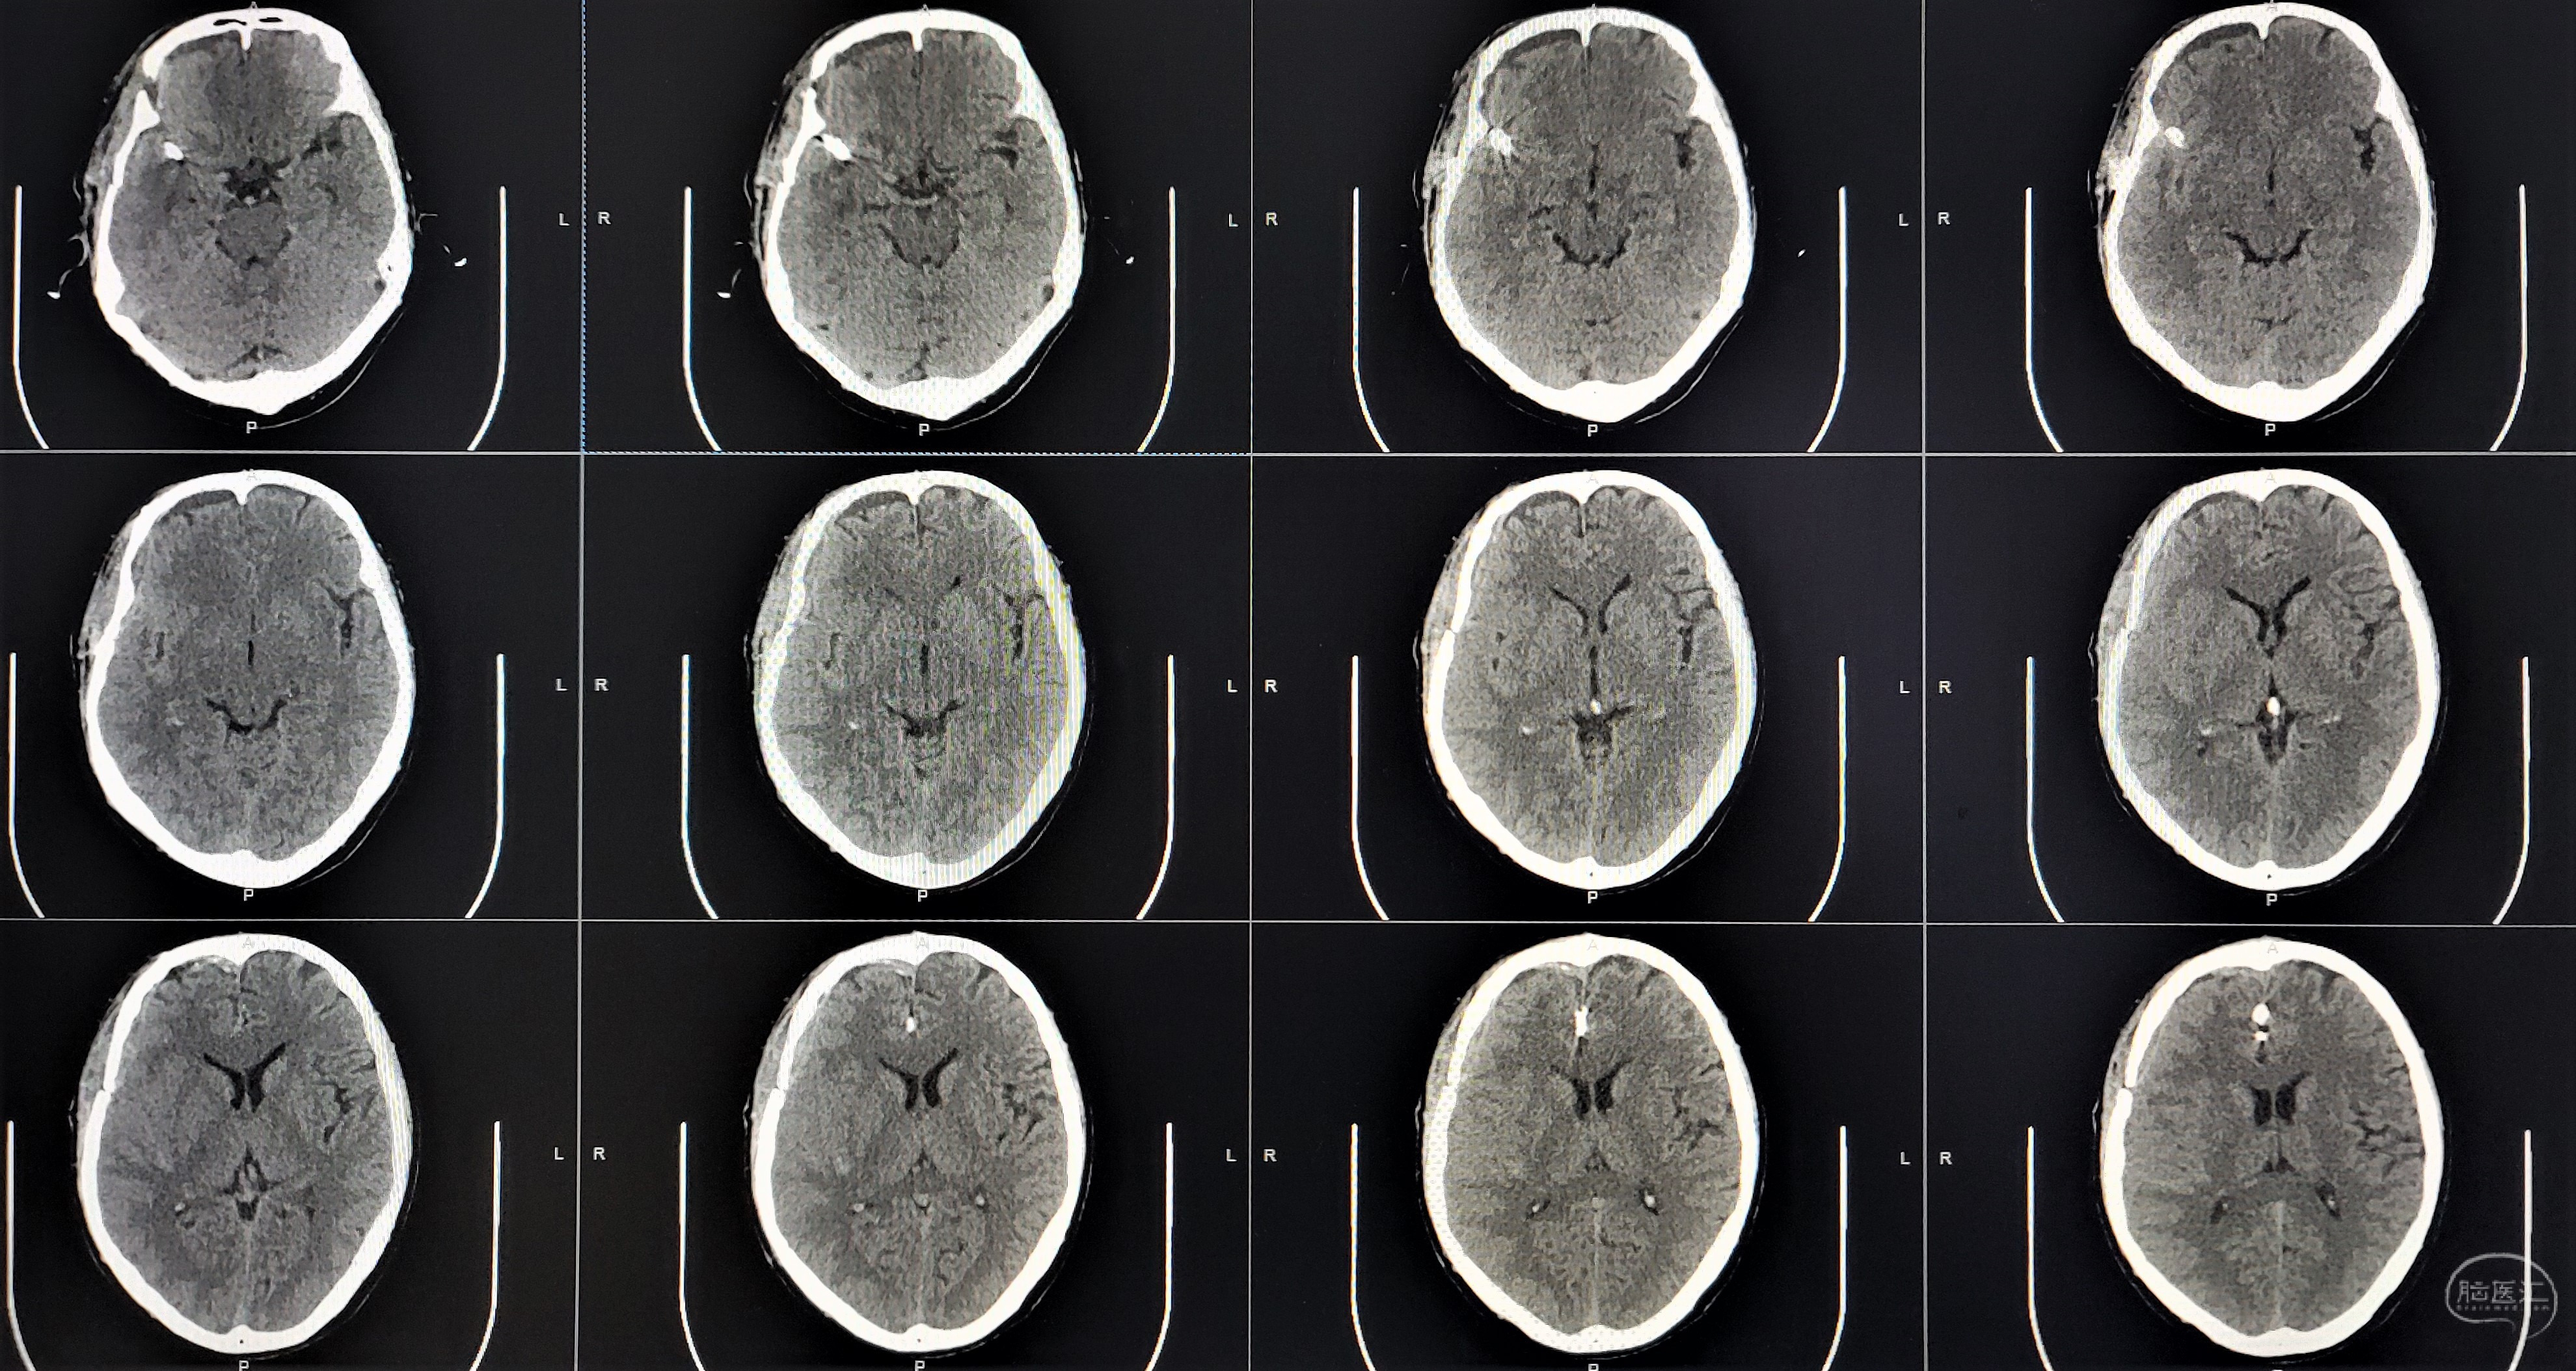

术前CT显示右侧外侧裂蛛网膜下腔出血。

术后第一天CT,血肿大部分清除,无明显脑梗死。